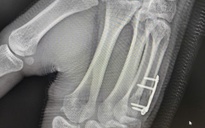

Trường hợp 2 là nữ bệnh nhân bị gãy hở phức tạp vùng khuỷu và cẳng tay. Các bác sĩ đã áp dụng chiến lược "Phẫu thuật hai thì". Thì 1: Cắt lọc, cố định tạm thời để ngăn ngừa nhiễm trùng. Thì 2: Điều trị thực thụ, kết hợp xương bằng nẹp vít và kim Kirschner để phục hồi giải phẫu, cố định khớp.

Kết quả vượt mong đợi, chỉ sau 2 tuần phẫu thuật, cả hai bệnh nhân đều có vết mổ liền tốt và đã phục hồi được phần lớn biên độ vận động khớp khuỷu. Đây là minh chứng cho sự chuẩn bị kỹ lưỡng, rút ngắn thời gian mổ và chăm sóc hậu phẫu tích cực tại bệnh viện.

Theo BSCKII Phạm Văn Nhật, Khoa Chấn thương Chỉnh hình - Bệnh viện An Bình, việc xử trí các ca gãy xương kèm trật khớp ở người lớn tuổi phải đối mặt với nhiều vấn đề phức tạp vì chất lượng xương kém: Xương giòn, gãy nhiều mảnh khiến việc nắn chỉnh và cố định cực kỳ khó khăn. Tổn thương mô mềm nặng: Dây chằng, cơ và da bị hư hại sâu, dễ dẫn đến nhiễm trùng hoặc mất vững khớp. Bệnh lý nền phức tạp như các bệnh như tăng huyết áp, đái tháo đường, Cushing... làm tăng rủi ro trong và sau mổ.